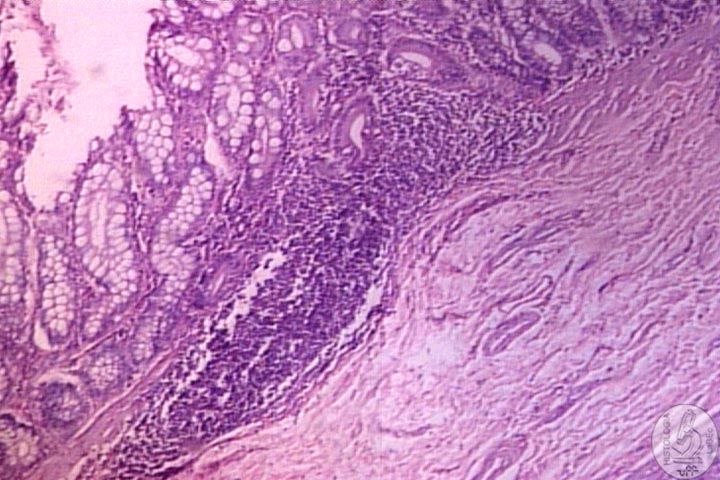

Tubo Oco composto por um lúmen, cujo diâmetro é

variável, circundado por uma parede formada por quatro

camadas distintas:

Mucosa

• Revestimento Epitelial

• Lâmina Própria: Tecido Conjuntivo Frouxo,

rico em vasos sanguíneos e linfáticos, além

de células musculares Lisas

Muscular

da Mucosa

• Separa a Mucosa da Submucosa

Geralmente constituída de duas subcamadas delgadas de células

musculares lisas |

Submucosa

•

Tecido Conjuntivo Frouxo com muitos vasos sanguíneos e

linfáticos

• Presença do Plexo Nervoso Submucoso ou Plexo de

Meissner

Pode conter Glândulas e Tecido Linfóide |

Camadas

Musculares

• Células musculares Lisas orientadas em Espiral,

divididas em duas Subcamadas Circular Interna e Longitudinal Externa

Entre as duas Subcamadas encontra-se o Plexo Nervoso Mioentérico

ou Plexo de Auerbach |

Serosa

Camada Delgada de Tecido Conjuntivo Frouxo, rica em vasos sanguíneos,

linfáticos e tecido Adiposo

• Revestido por uma fina camada de Epitélio Pavimentoso

Simples denominado Mesotélio |